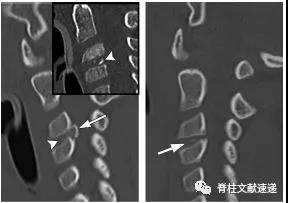

图注:49岁男性,极外侧腰椎间盘突出症。

图注:49岁男性,极外侧腰椎间盘突出症,有黑色素瘤病史。(e) 轴位PET图像显示病灶部位有FDG摄取,怀疑黑色素瘤转移。经过3周的保守治疗,病人的病情有所好转。临床上并没有黑色素瘤诊断。